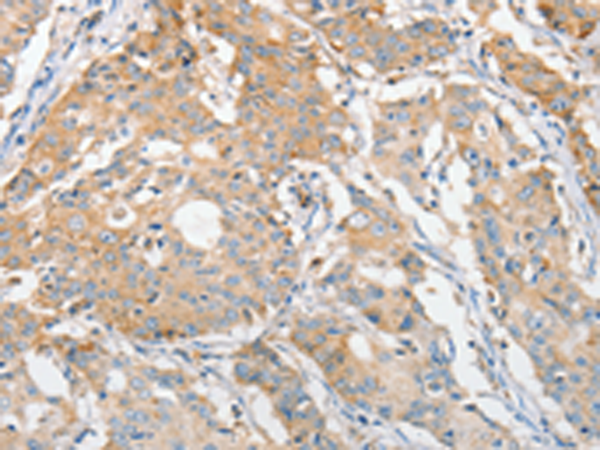

分类: 科研抗体货号: P07833别名: CALS-7; MDS015; ALS2CR1应用: WB,IHC反应种属: Human, Mouse, Rat